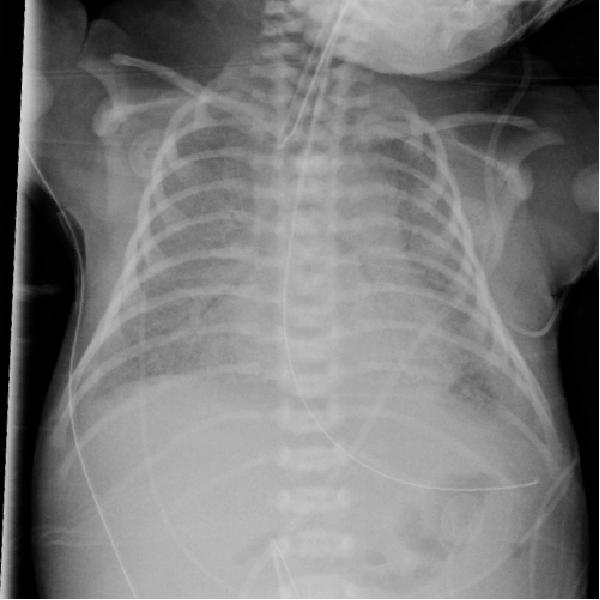

1、28周早产儿,呼吸困难1天。

可见双侧对称弥漫分布的的颗粒状高密度影。可见支气管充气。

这就是典型的新生儿特发性呼吸窘迫综合征(RDS)。

其特征性 X 线表现为:

1)两肺野透光度普遍减低,呈毛玻璃状,或两肺野中内带多发细小颗粒状或小结节和网状影,下肺野较上肺野更为显著;

2)气管支气管充气显著,在两肺野密度普遍性增加的对比之下显示更为清楚;

3)胸廓扩张良好,横膈位置正常。 对怀疑本病者,短期(1 ~ 2h)连续拍片观察,对诊断意义较大;有文献提出凡 6~ 12h 胸部影像尚无确切网粒阴影者,可排除本病。